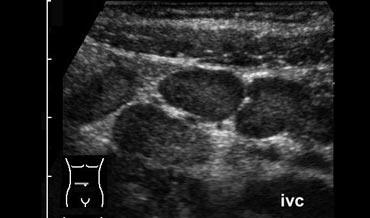

Viêm hồi tràng do Crohn với đường rò (mũi tên) vào ruột thừa lân cận. Lưu ý sự mất cấu trúc lớp khu trú của thành hồi tràng và các khối mỡ viêm xung quanh lớn (fat).

Trên siêu âm, thành hồi tràng dày lên rõ rệt, nhu động giảm hoặc mất hoàn toàn và không thể ép xẹp được.

Điển hình, tất cả các lớp thành ruột đều bị tổn thương và cấu trúc lớp thường bị phá vỡ khu trú, dấu hiệu sớm nhất là sự thay đổi giảm âm ở lớp dưới niêm mạc.

Có hiện tượng viêm mạc treo ruột và mạc nối, biểu hiện là mô tăng âm, không thể ép xẹp, nằm kề cận hồi tràng.

Các dải giảm âm trong mô tăng âm gợi ý các đường hoại tử mỡ, có thể là dấu hiệu báo trước của sự hình thành đường rò (Hình).